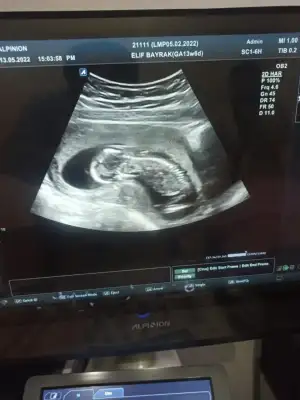

Bu erkek oluyor galiba değil mi ?12+1 çıktı

Kiz olunca üç çizgi oluyormus bunda 2 var sanki

Nuba göre bakılmıyor mu bu haftalarda bilmiyorum kiBu erkek oluyor galiba değil mi ?